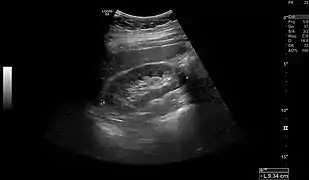

Normal adult right kidney as seen on abdominal ultrasound with a pole to pole measurement of 9.34 cm.

Renal ultrasonography is essential in the diagnosis and management of kidney-related diseases.[39] Other modalities, such as CT and MRI, should always be considered as supplementary imaging modalities in the assessment of renal disease.[39]